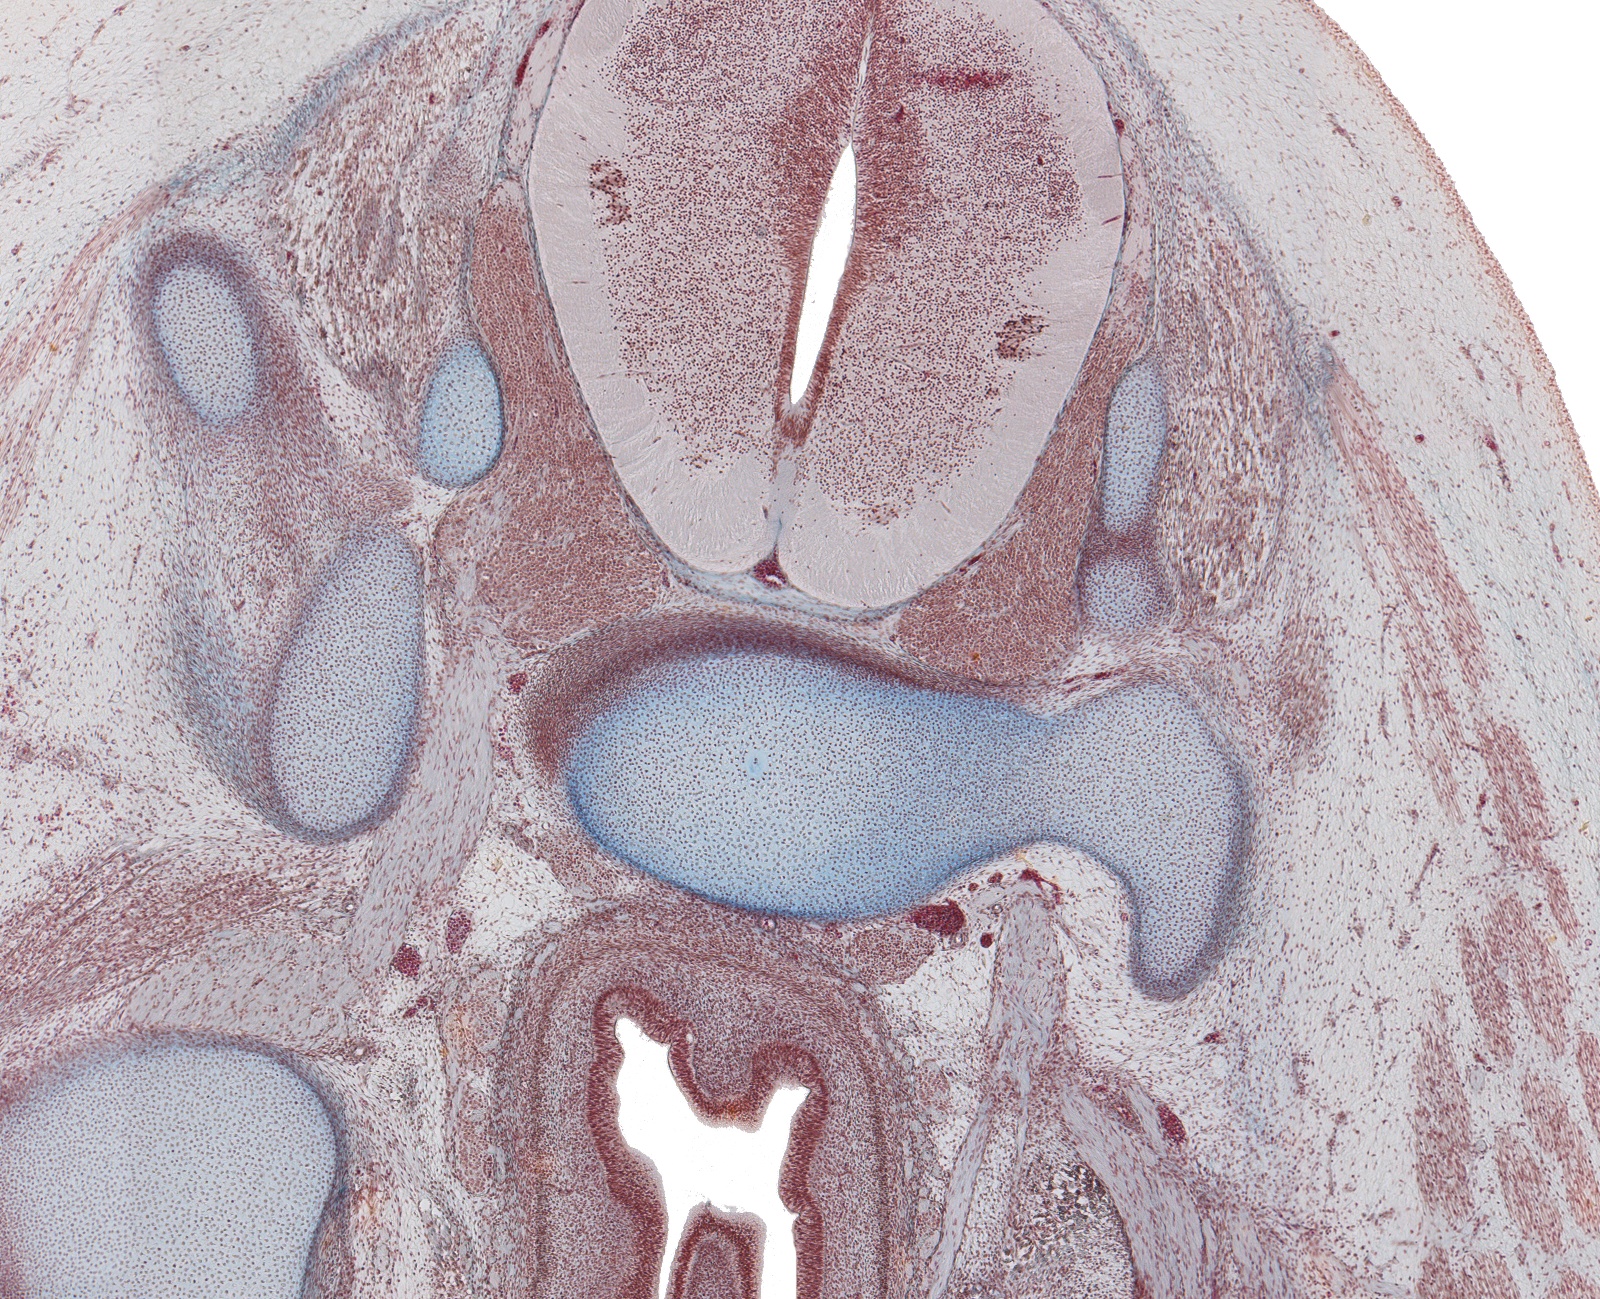

S-2 Spinal Cord, Rectum and Sacral Plexus

Carnegie Embryo #9226

200-01-01